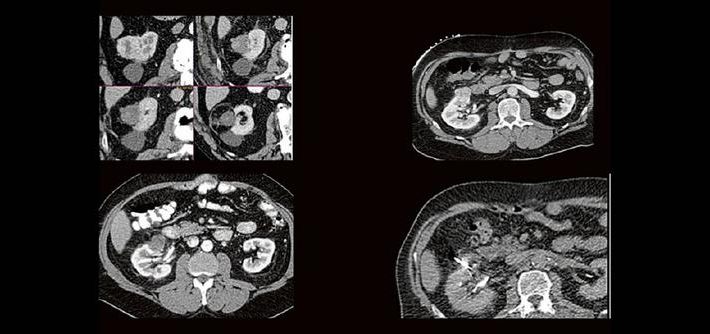

Thermoablation von Nierentumoren (Webinar | Online)

Dr. med. Sascha Alexander Pietruschka Die Anwendung von ablativen Verfahren hat sich in der klinischen Praxis etabliert. Nierentumoren bieten sich für den Einsatz von RFA und Mikrowelle an. Im Dietrich Bonhoeffer Klinikum Neubrandenburg blicken wir auf 15 Jahre Erfahrung mit mehr als 100 RFA/Mikrowellenablationen von Nierentumoren zurück. Im Vortrag werden die eigenen Erfahrungen und Ergebnisse […]